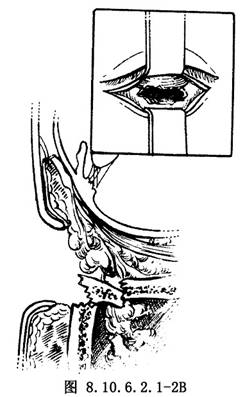

(1)皮肤切口:在距下睑睫毛下缘3mm处,作皮肤水平切口,先用蓝色染料作标记,局部浸润麻醉,助手用手指压迫眶下动脉,切口深达眼轮匝肌及睑板,分开眼轮匝肌,暴露眶隔并剥离,直达眶缘,然后沿睑板下缘切开眶缘处骨膜,循眶下壁向后剥离,并用器械将骨膜抬起,暴露骨折区(图8.10.6.2.1-2A、B)。此切口的优点是术中游离被嵌顿的眶内组织比较容易,手术后瘢痕很少。